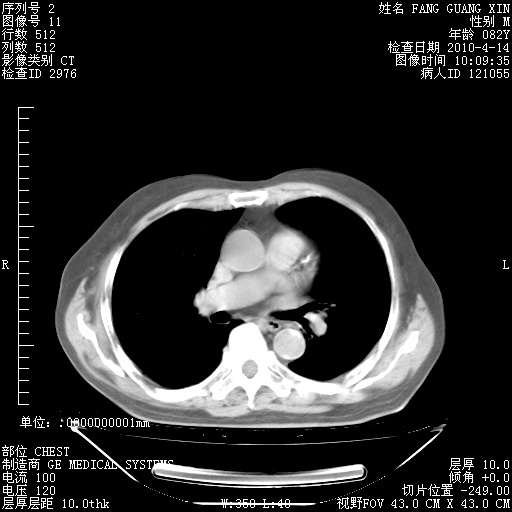

4月14日肺部CT